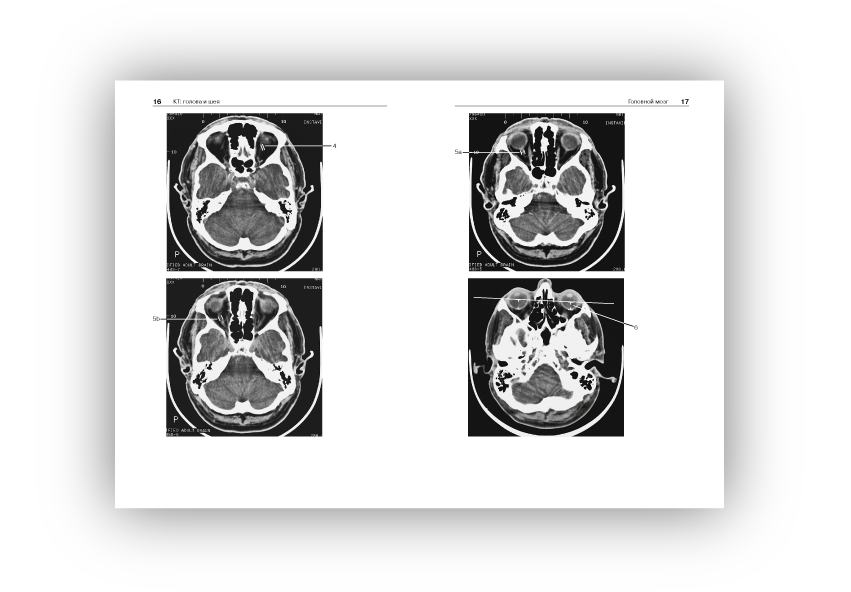

Норма при КТ- и МРТ-исследованиях: пер. с англ./ Торстен Б. Мёллер, Эмиль Райф; под общ. ред. Г.Е.Труфанова, Н.В.Марченко.- 3-е изд. - М.: МЕДпресс-информ, 2016. - 255, [1] с.: ил..

Широкое использование в современной клинической практике компьютерной томографии и магнитно-резонансной томографии как решающих методов диагностики при многих болезнях, относящихся к различным клиническим специальностям и разным анатомическим областям, выдвигает на первый план проблему границ между нормой и патологией при трактовке изображения на срезах.

Помочь врачу - специалисту, составляющему заключение на основании анализа изображений, полученных при КТ- и МРТ-исследованиях, - основная задача этой книги, которая как бы продолжает ранее вышедшую книгу Норма при рентгенологических исследованиях. Каждому из названных методов посвящен самостоятельный ее раздел, охватывающий все исследуемые анатомические области (голова и шея, грудная клетка и т.д.).